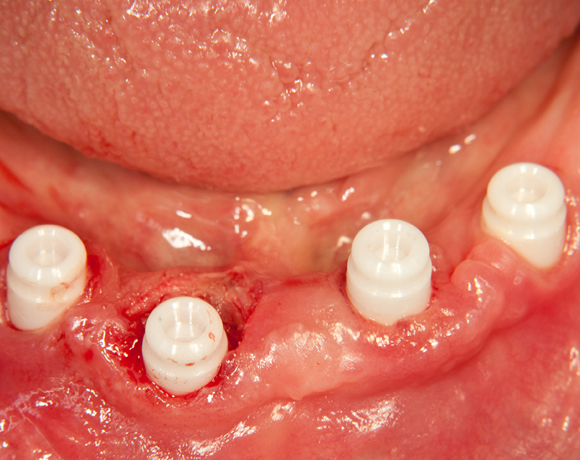

Bild 01: Nach einem Jahr wurden noch zwei Implantate ergänzt, für einen festeren Halt